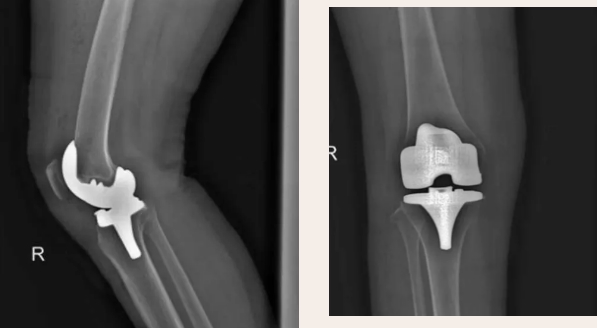

刘阿姨今年64岁,常年受膝盖疼痛困扰,随着时间的推移,刘阿姨的腿部变形,膝关节已经严重畸形。平时坐着、躺着还好,一旦站起来或者走几步路,就腿疼不止,别说正常的体力活不能干,就连日常生活都受到影响。现在蹲起困难的她只能在家坐坐,出行受到了极大的限制。为了减轻日常生活中膝盖带来的疼痛,这次刘阿姨下决心要好好治治,听闻淄博市第四人民医院骨科不错,于是特地前来求医,找到了骨科二组的王宁副主任。王宁对刘阿姨的膝盖进行了全面检查,根据病情分析判断为膝关节骨性关节炎,考虑刘阿姨的诉求,决定对她实施膝关节置换术。术后为刘阿姨制定了科学的康复计划,经过康复锻炼后刘阿姨恢复了正常生活,行走、下蹲均无疼痛。

膝关节骨性关节炎是中老年的常见病、多发症。其发病原因一是膝关节的过度磨损所导致的关节软骨损伤。治疗上,轻度甚至中度膝关节骨性关节炎可以通过非手术治疗缓解症状,部分严重的膝关节骨性关节炎患者须进行人工膝关节置换才能收到满意的疗效。双膝关节置换术是目前国际上治疗骨性关节炎的最终方法。手术关节置换治疗膝关节骨性关节炎在治疗疼痛和恢复关节功能等方面效果显著。